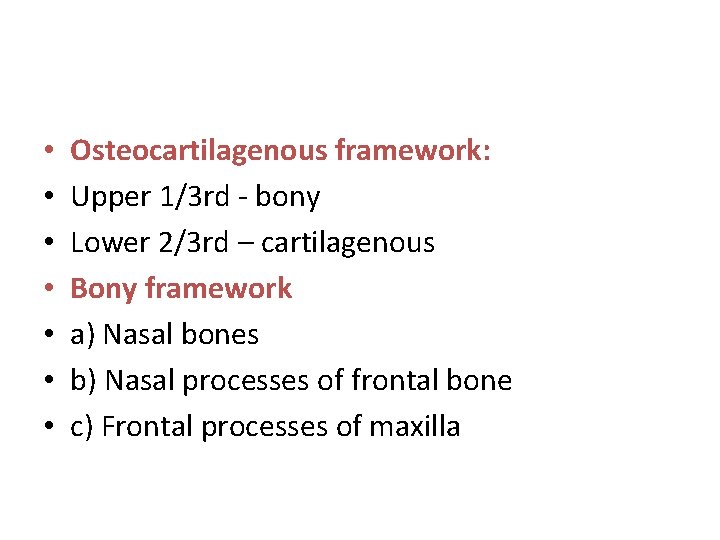

• • Osteocartilagenous framework: Upper 1/3 rd - bony Lower 2/3 rd – cartilagenous Bony framework a) Nasal bones b) Nasal processes of frontal bone c) Frontal processes of maxilla

• • • Cartilagenous framework a) Upper lateral cartilages b) Lower lateral cartilages (alar cartilages) c) Lesser cartilages (sesamoid cartilages) d) Septal cartilage